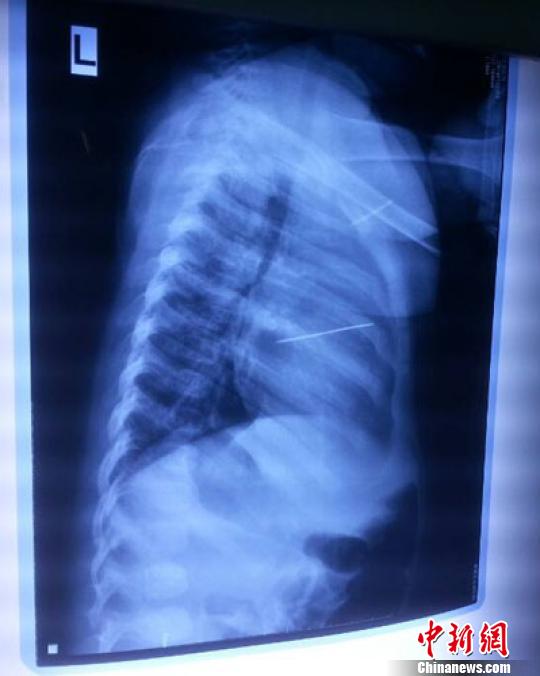

女嬰胸片提示心臟里面扎了一個縫衣針 蔡迅翔 攝

醫(yī)院胸心外科主任翟波介紹說,1月22日,小患者彤彤因為發(fā)燒抽搐來醫(yī)院就診,常規(guī)檢查時發(fā)現(xiàn)孩子心臟里面扎了一個縫衣針。

“第二天上午,我們做了個緊急彩超檢查,發(fā)現(xiàn)針是從患者右心室表面刺入,穿破室間隔,到達(dá)左心房,中間還有一部分損害到二尖瓣。于23號下午,我們就做了一個緊急手術(shù),手術(shù)中發(fā)現(xiàn),這枚針已經(jīng)刺入心臟,沒入了右心室的下面,表面已經(jīng)看不到針了,僅能看到一個小針眼,還在往外滲血,一點(diǎn)一點(diǎn)的滲,心包腔里面大概有100多毫升的出血,心包上一個洞,針在右心室表面刺入以后,穿過室間隔,在二尖瓣的上方,進(jìn)入了左心房,在針的四周,有很多纖維沉積物,包繞著這枚針。”翟波說,他們把針取出來以后,測量了一下,長度大概是五厘米,同時發(fā)現(xiàn)這個針給患者左心房的后壁造成了一定的損傷,左心房的后壁已經(jīng)損傷了三分之二,還剩下有左心房的外膜,很薄的一層,如果這一層再破的話,這個孩子將會引起大出血,很快就會死亡。